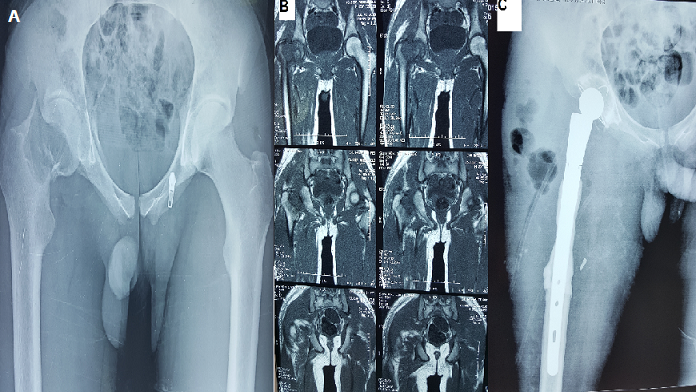

Fracture du col fémoral révélatrice d’un ostéosarcome de la hanche traitée par une prothèse massive

Il s'agit d'un patient de 22 ans sans antécédent pathologique notable qui a présenté une semaine avant son hospitalisation des douleurs au niveau de sa hanche droite avec impotence fonctionnelle totale du membre inférieure droit sans notion d'altération d'état général. L'examen clinique fait à l'admission a objectivé une douleur à la palpation et à la mobilisation de la hanche droite. La radiographie standard (A) et le scanner de la hanche (B) ont objectivé une fracture du col fémoral droit sur os pathologique. Une biopsie de la tumeur a été fait revenant en faveur d'un ostéosarcome épiphyso-métaphysaire cervico-céphalique droit. Le bilan d'extension locorégional ne montre pas une autre localisation ou des métastases. Le patient a bénéficié de Sept séances de Chimiothérapie néo adjuvante puis d'une résection carcinologique de la tumeur et une reconstruction par prothèse de hanche massive (C).